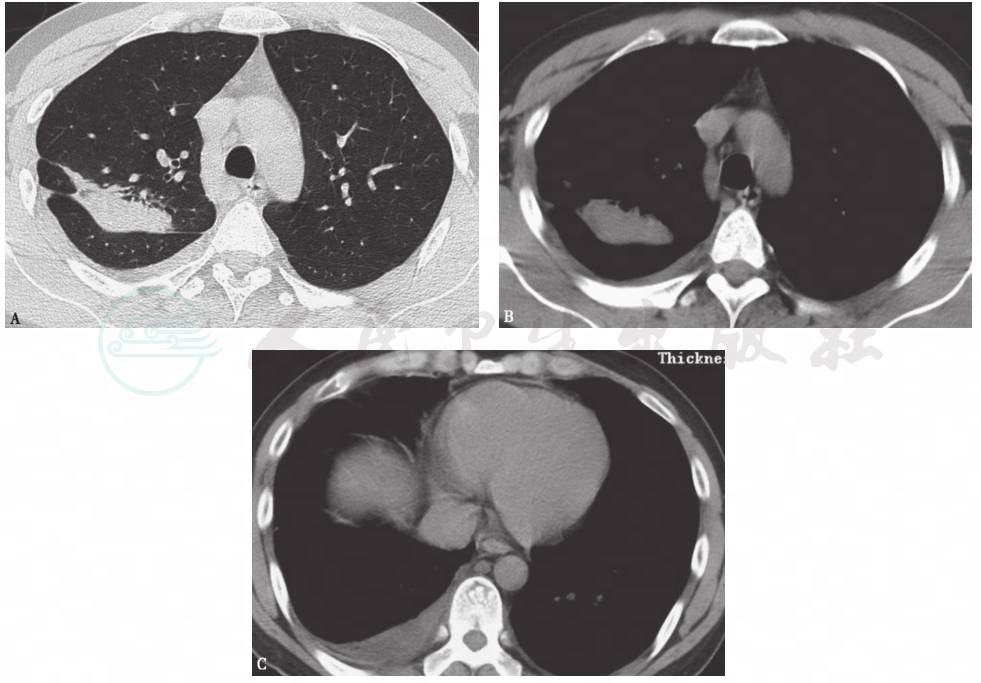

胸部CT平扫:左下肺膨胀不全,左侧胸腔积液,两肺索条影(图1)。

图1 胸部CT表现

胸部CT显示左下肺膨胀不全,左侧胸腔积液